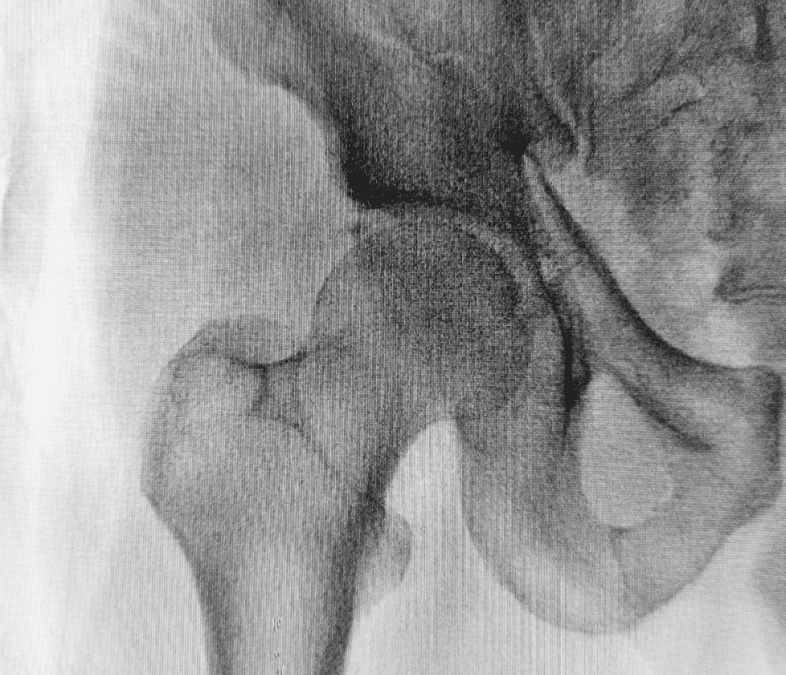

Calcola il tuo “Rischio Osteoporosi”

👉 Clicca qui: https://tripetto.app/run/1GK4351368 «Nel corso della vita, circa il 40% della popolazione incorre in una frattura di femore, vertebra o polso, in maggioranza dopo i 65 anni. In Italia, il 23% delle donne oltre i 40 anni e il 14% degli uomini con più di...